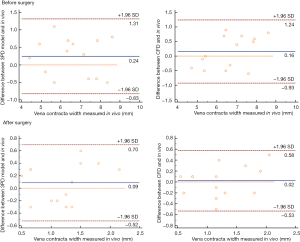

In all patients, the grade of MR and the VCW measured in vitro and in vivo before surgery were highly consistent (Tables 2,3, Figure 6). With the 3DP model, 3 patients were assessed as moderate MR, 4 as moderate-to-severe MR, and 28 with severe MR. Only one patient was assessed as moderate MR in vitro but had moderate-to-severe MR in vivo, and one patient was assessed as moderate-to-severe by CFD but was severe in vivo (Table 2).

Surgical simulations were successfully done in vitro (both dynamic 3DP model and CFD) for all 14 patients who had MVR. The grade of MR and the VCW showed a significant decline after the surgical simulation (Figure 7). The difference between the data obtained in vitro and in vivo was not statistically significant (P<0.05, Table 3, Figure 6).

Comparison of surgical simulation using the 3DP dynamic model and CFD

Data obtained using the 3DP dynamic model and CFD was highly consistent. The difference in VCW between the 3DP model and CFD was not statistically significant (P<0.05). However, compared with CFD, it took more time for the surgical simulation and hemodynamics testing in the 3DP model, with an average time of about 6 hours for 1 patient, compared with only 1 hour with CFD (Table 7).